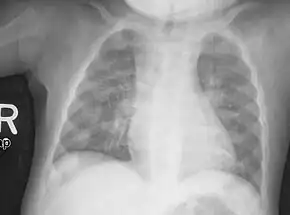

| X-ray of a two-year-old with rickets, with a marked bowing of the femurs and decreased bone density | |

An X-ray or radiograph of an advanced sufferer from rickets tends to present in a classic way: the bowed legs (outward curve of long bone of the legs) and a deformed chest. Changes in the skull also occur causing a distinctive "square headed" appearance known as "caput quadratum".[14] These deformities persist into adult life if not treated. Long-term consequences include permanent curvatures or disfiguration of the long bones, and a curved back.[15]